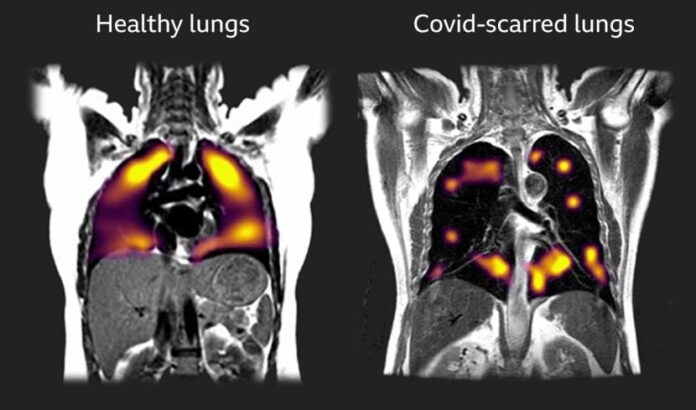

They noted that hyperpolarised xenon MRI (XeMRI) scans had found abnormalities in the lungs of some COVID-19 patients more than three months — and in some cases, nine months — after leaving hospital, when other clinical measurements were normal.

The 129Xe MRI is pinpointing the parts of the lung where the physiology of oxygen uptake is impaired due to long standing effects of COVID-19 on the lungs, even though they often look normal on CT scans.

“Our follow-up scans using hyperpolarised xenon MRI have found that abnormalities not normally visible on regular scans are indeed present, and these abnormalities are preventing oxygen getting into the bloodstream as it should in all parts of the lungs,” Gleeson said.